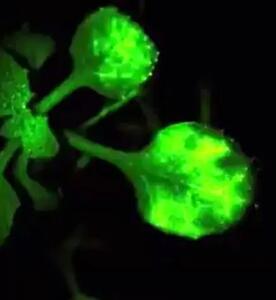

اندیشه معاصر - انقلاب در علم پزشکی/ احیای بینایی با استفاده از پیوند سلول های بنیادی برای نخستین بار در جهان اندیشه معاصر

دانشمندان ژاپنی توانستهاند با پیوند سلولهای بنیادی گرفته شده از سلولهای خونی انسان، بینایی را به افرادی که دچار آسیب قرنیه شدهاند، بازگردانند.